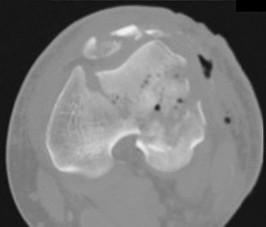

This module contains 20 advanced orthopedic multiple-choice questions meticulously developed to mirror the Arab Board of Orthopedic Surgery examinations. These questions are derived from the clinical teaching case: 1.3 Skeletal Dysplasias with Major Involvement of the Spine . . . . . . . . . . . . . . . . . . . . . . . . 11.